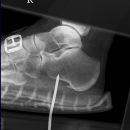

Calcaneus